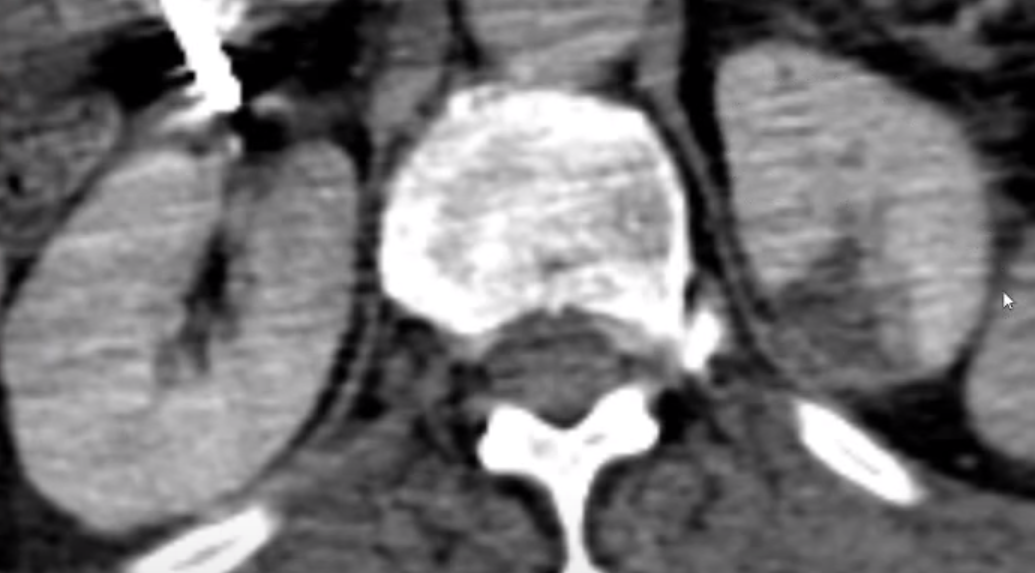

Fibrilação atrial; Dor lombar

Infarto renal.

Opacidade triangular em cunha; realce cortical periférico.